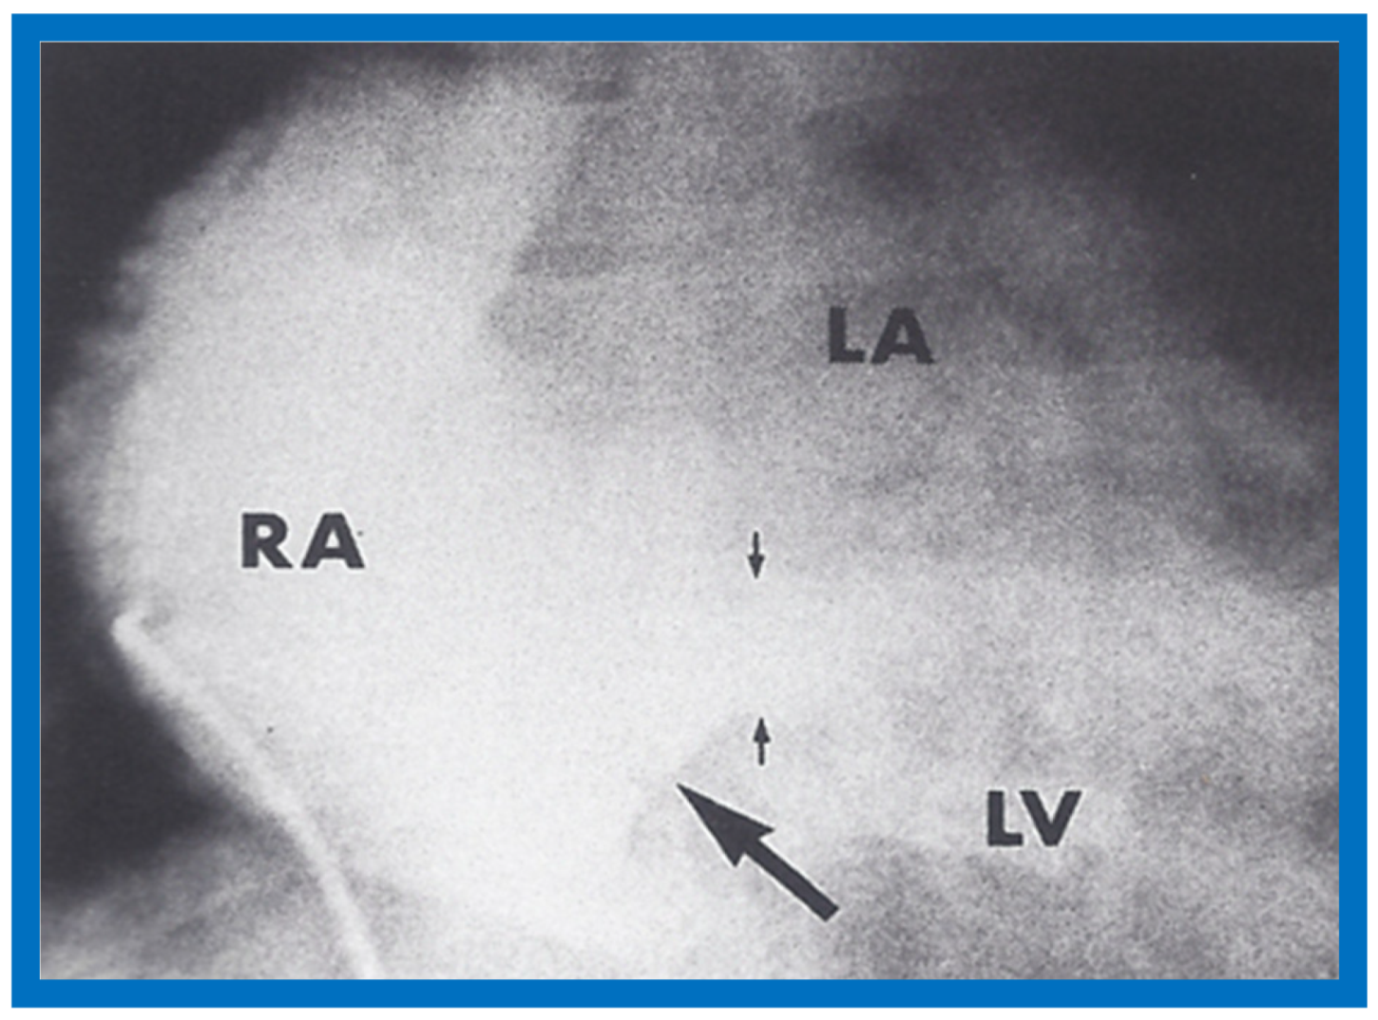

At the age of 8 months, cardiac catheterization with selective cineangiography was performed. The left atrium (LA) was catheterized via a tight patent foramen ovale, and the catheter was advanced from the LA into the superior vena cava (SVC) and into both right and left innominate veins. The right heart saturations were low (60–62%) without any evidence for a step up. The pulmonary venous saturations were normal (98%) with a step down in the left atrium and left ventricle (79%). The pressures in all cardiac chambers were normal (See Table 1 of [2]). Selective cineangiography into the right (Figure 6A,B) and left (Figure 6C) innominate veins confirmed the diagnosis of anomalous connection of the right SVC to the LA. No persistent left SVC was identified. Because of a lack of other symptoms and only mild polycythemia (hemoglobin of 15 gm%), surgical correction was deferred at that time with a plan for surgery at a later date.

Figure 6.

Angiographic frames from injections into the right innominate (A,B) and left innominate (LInV) (C) veins demonstrating direct opacification of the right superior vena cava (SVC), left atrium (LA), left ventricle (LV) and aorta (Ao) without opacification of the right heart structures. C, Catheter. Reproduced from Truman T.A., Rao P.S., Kulungara R.J. [2].